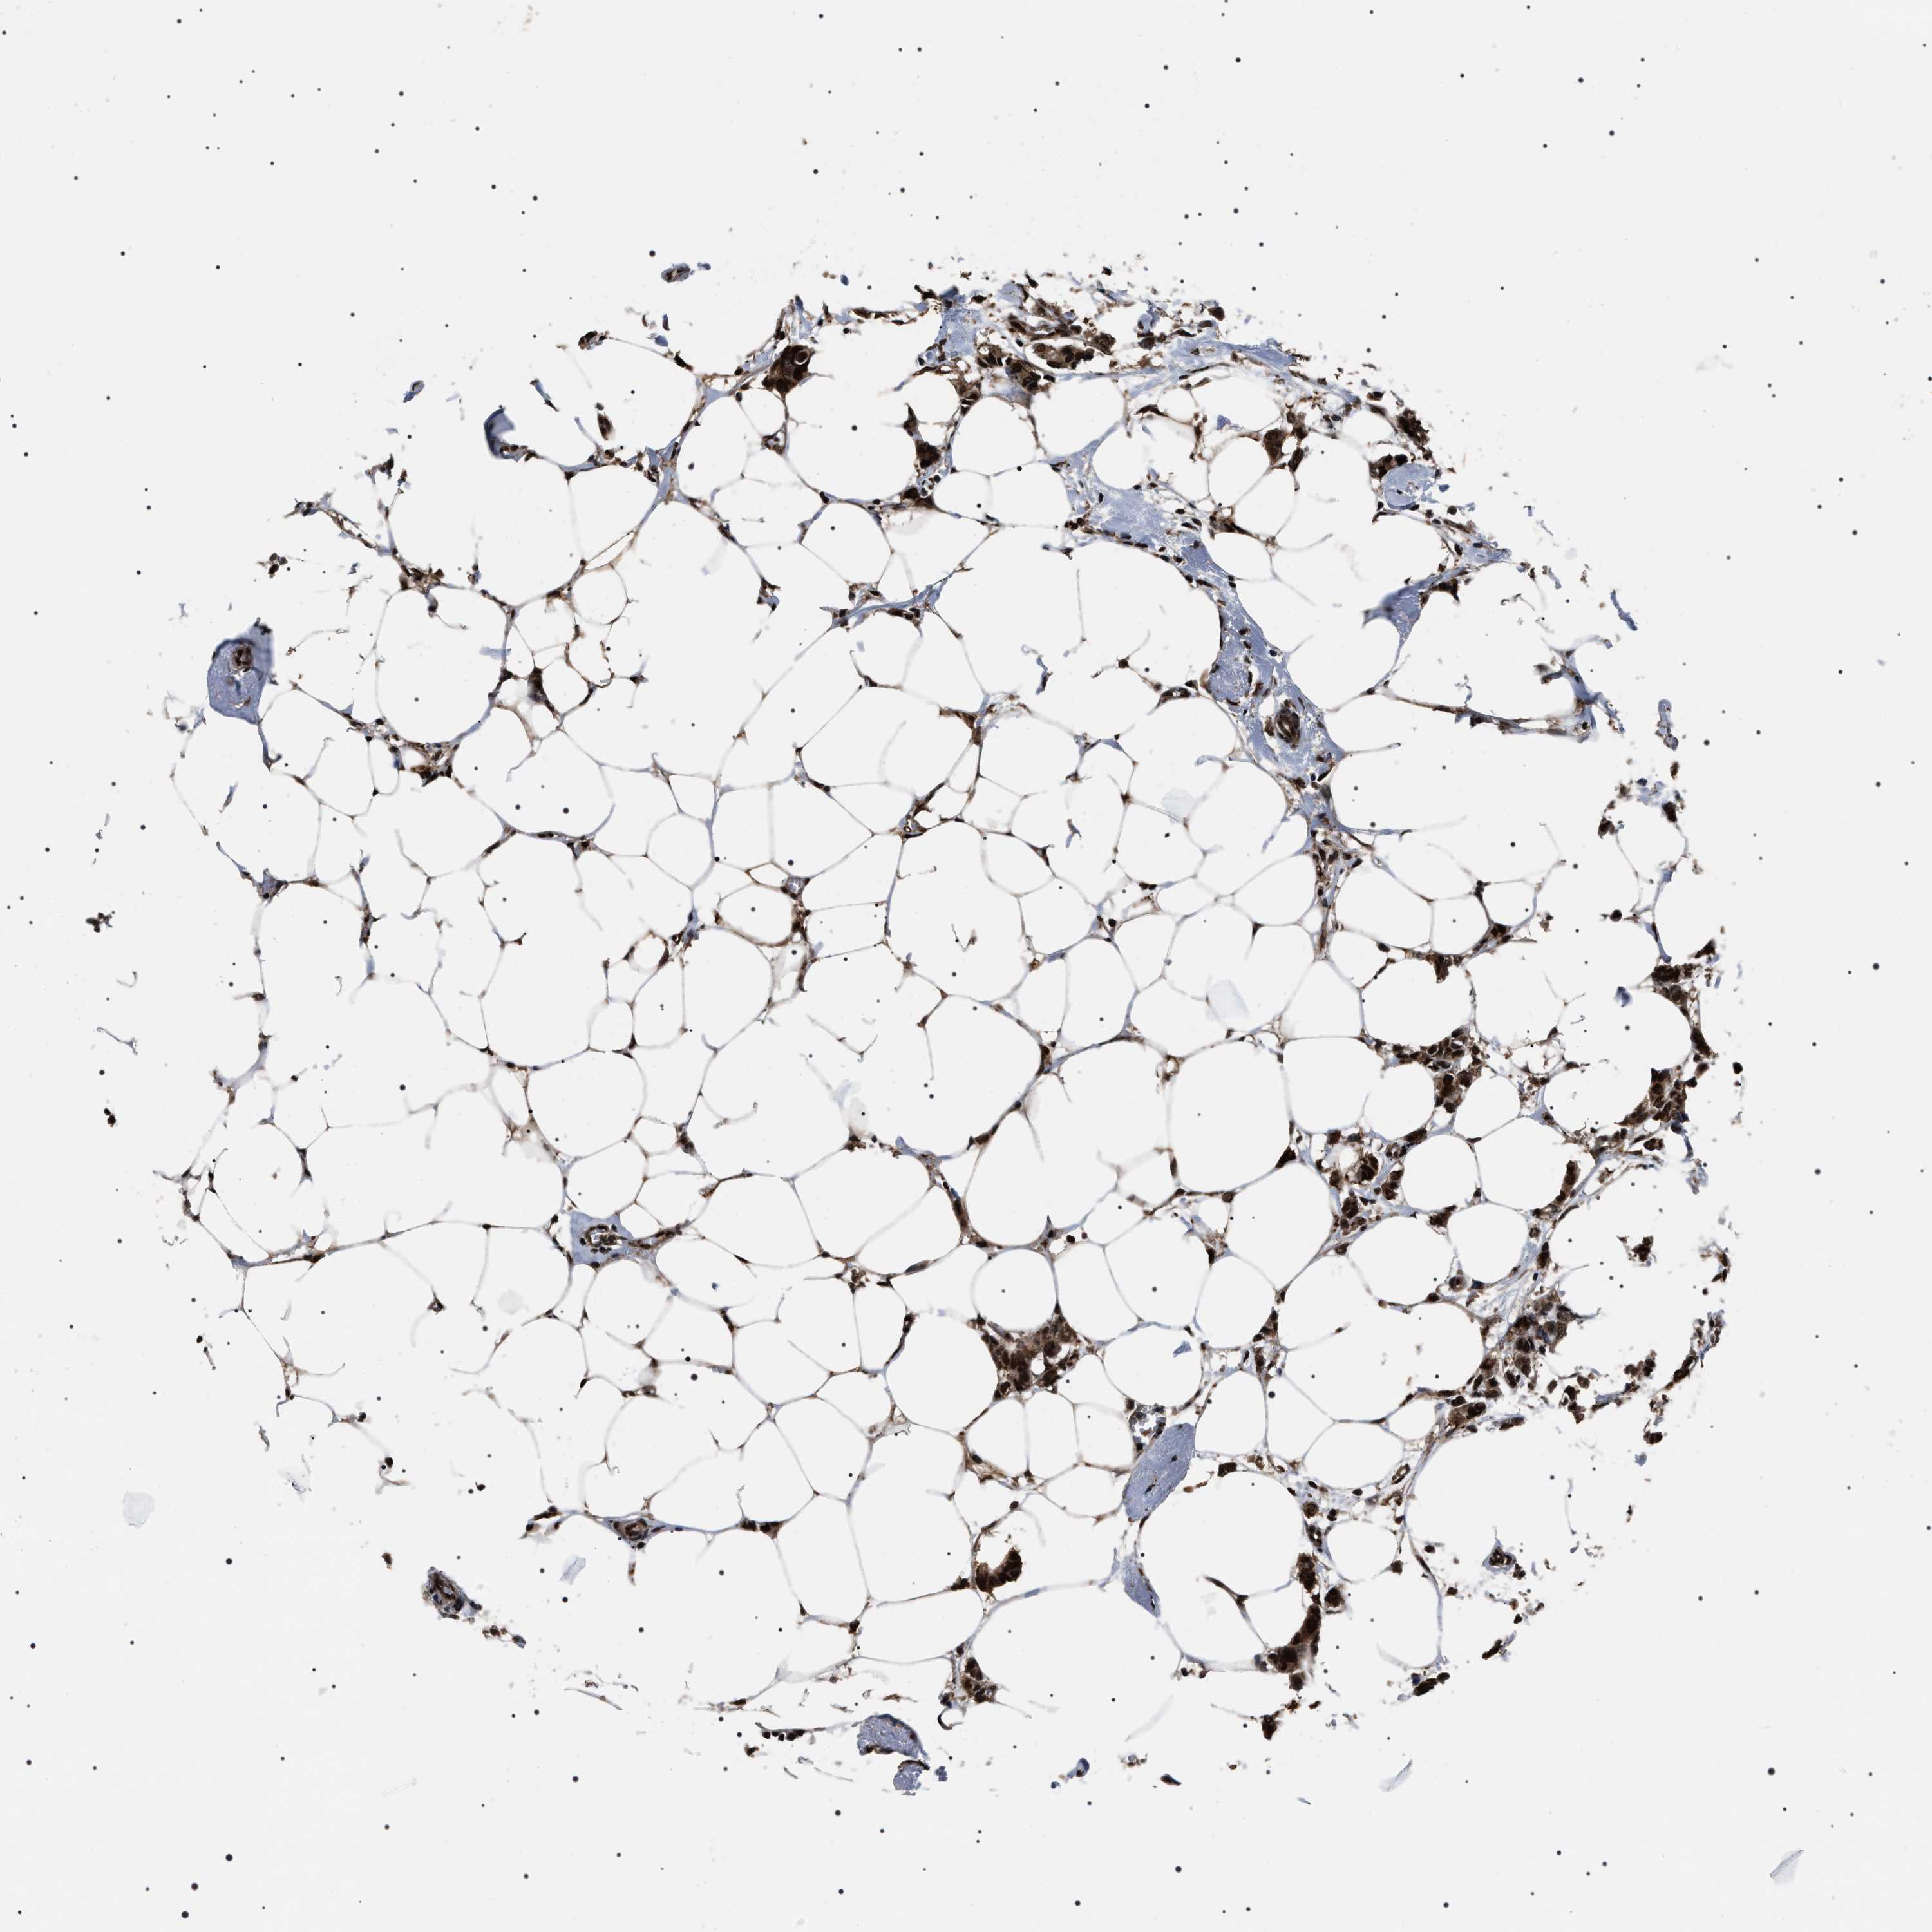

CANCER BREAST CANCER Show tissue menu

BRCA TCGA BRCA VALIDATION PROTEIN EXPRESSION

ANTIBODIES

AND

VALIDATION